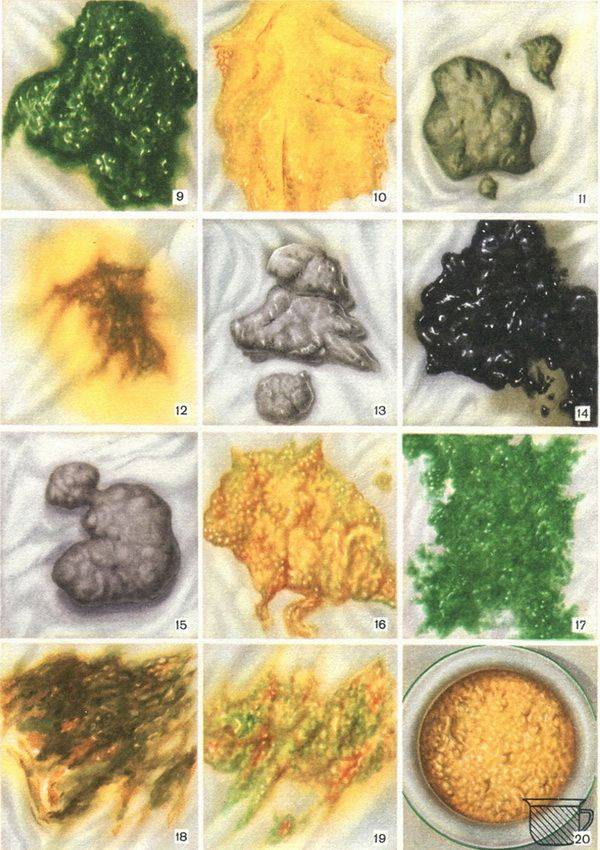

Медицинские аспекты мекония в околоплодных водах